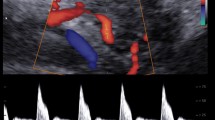

Fetal echocardiography was performed before and within 2.5 h after IUT (median 69 min, interquartile range 54–79) by two experienced operators (KFW and LH) using a GE Vivid-i ultrasound imaging system with a 3S-RS (1.9–3.8 MHz) phased array transducer (GE Vingmed Ultrasound AS, Horten, Norway) or a Vivid S6 ultrasound imaging system with a M4S-RS (1.9–4.1 MHz) phased array transducer (GE CV Ultrasound, Haifa, Israel). All cTDI recordings were obtained in an apical or basal four-chamber view and cine-loops of consecutive cardiac cycles were stored for off-line analysis. Acquisition was optimized to obtain a high frame rate and the incident angle was kept as close to the long-axis of the heart as possible (deviation always <30o). Off-line analysis was performed in EchoPAC version 201 (GE Vingmed Ultrasound AS, Horten, Norway). Regions of interest (ROIs) were placed at the atrioventricular plane (AV-plane) in the left (LV) and right ventricular (RV) walls and the interventricular septum (IVS) (Fig. 1). ROI size was adjusted to gestational age [15]. With the aim to reduce variability all ROIs were placed by one operator (LH) and positioned with the AV-plane reaching approximately one third into the ROI at end-systole.

a. The position of regions of interest (ROI) with size 6 × 4 mm in an anemic fetus before intrauterine transfusion at 34 weeks of gestation. The left panel indicates the position of ROIs in the four-chamber view of the fetal heart at end-diastole. The right panel shows the myocardial velocity trace derived from the right ventricular wall. b. The same myocardial velocity trace analyzed by the automated algorithm. Colors indicate different phases in the cardiac cycle: dark blue – atrial contraction, light green – pre-ejection, red – ventricular ejection, dark green – post-ejection, yellow – rapid ventricular filling and light blue – slow ventricular filling. Sm, peak myocardial velocity during ventricular ejection (systole); Em, peak myocardial velocity during rapid ventricular filling; Am, peak myocardial velocity during atrial contraction

The peak myocardial velocity during atrial contraction (Am), ventricular ejection/systole (Sm) and rapid ventricular filling/early diastole (Em) were automatically obtained (Fig. 1). The Em/Am ratio was calculated. Fusion of Em and Am can take place at high heart rates, and such fusion events are detected by the algorithm. When fusion events are detected in a cardiac cycle the Em and Am cannot be separated and the value is omitted. All cardiac cycles available were evaluated by the algorithm and an average from all available cardiac cycles calculated. All measurements were performed for the LV, RV and IVS separately.